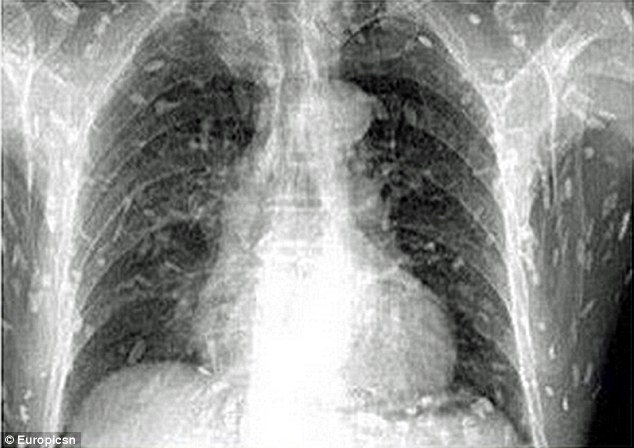

Sán làm "tổ" khắp người bệnh nhân. |

Tiến sĩ Yin đến từ bệnh viện Nhân dân số 8 cho biết trên trang web mags.com rằng, nếu ăn những thực phẩm chưa được nấu chín bị nhiễm trứng sán dây, con người có thể mắc bệnh nang sán khi sán dây xâm nhập vào mạch máu, thậm chí có thể đe dọa tính mạng khi sán nhiễm lên não bộ.